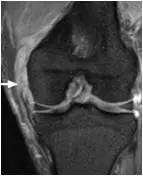

盘状半月板(Discoid Meniscus)

MRI-sag: 5mm层厚扫描时有3个或以上层面显示半月板前后角相连,形成蝴蝶结样改变Cor-半月板最窄处宽度大于14-15mm,外侧缘高于对侧2mm以上